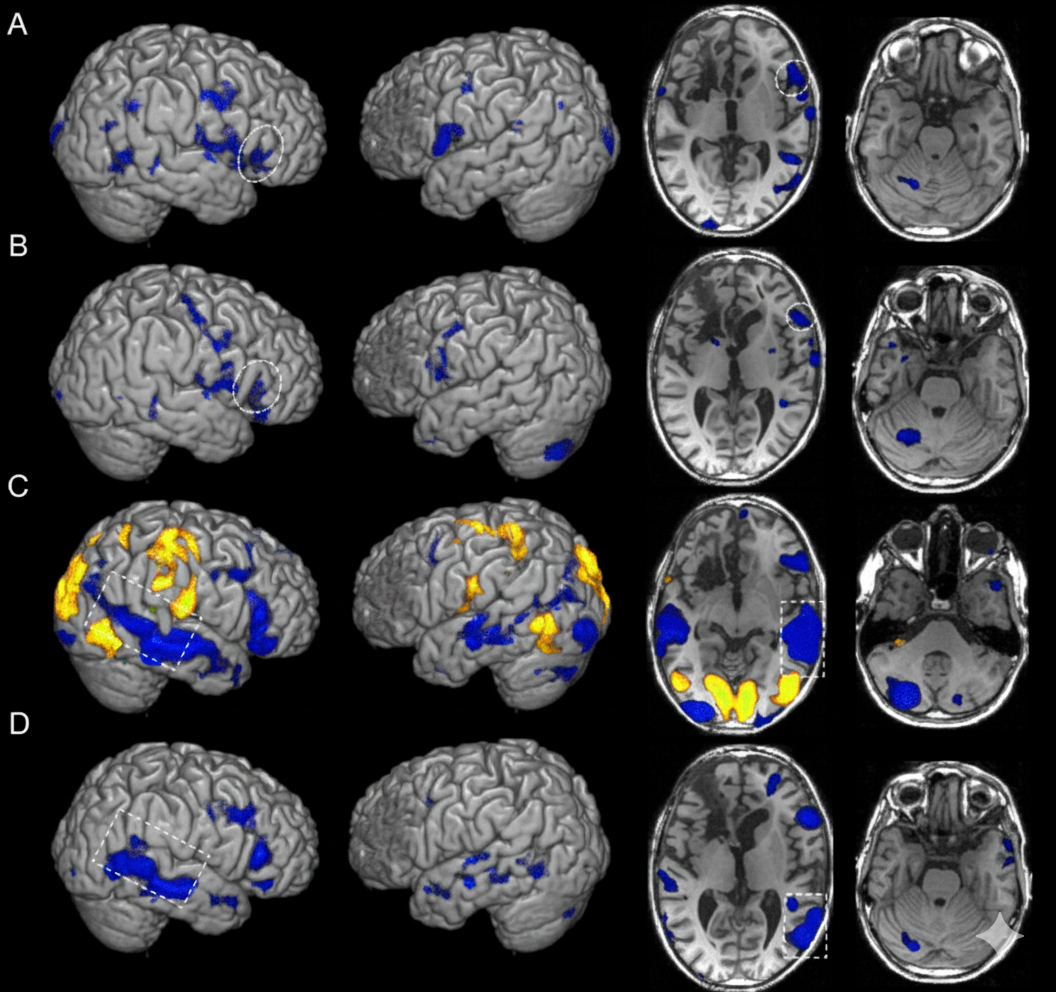

fMRI Scan TMS Depression Treatment

A large real-world study demonstrates that using fMRI brain scans to personalize TMS targeting will significantly improve outcomes for treatment-resistant depression—but the treatment works well either way.

How fMRI Personalizes the Target

Just as your fingerprints are unique, the precise architecture of your brain's functional networks varies from person to person. The DLPFC is a relatively large brain region that is responsible for many functions, so the "ideal" spot to stimulate within the DLPFC to reach the SGC could be a very different location for you than for someone else.

fMRI (functional magnetic resonance imaging) allows clinicians to map your brain's specific connectivity patterns. During a roughly 20-minute scan, patients simply rest while the MRI measures spontaneous fluctuations in brain activity—seeing how your brain naturally communicates with itself.

The analysis then identifies which locations in your DLPFC show the strongest anti-correlation (negative functional connectivity) with the SGC. This is your personalized target—the precise spot where stimulation is most likely to influence the depression-related network.